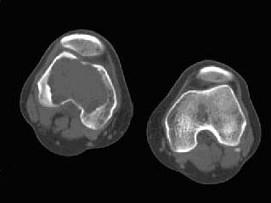

问题 患者,女,38岁,因右大腿远端部有疼痛,可摸到肿块,请结合所提供图像,选择最佳选项 ( )

选项 A、动脉瘤样骨囊肿 B、骨巨细胞瘤 C、骨囊肿 D、纤维异常增殖症 E、非骨化性纤维瘤

答案 B